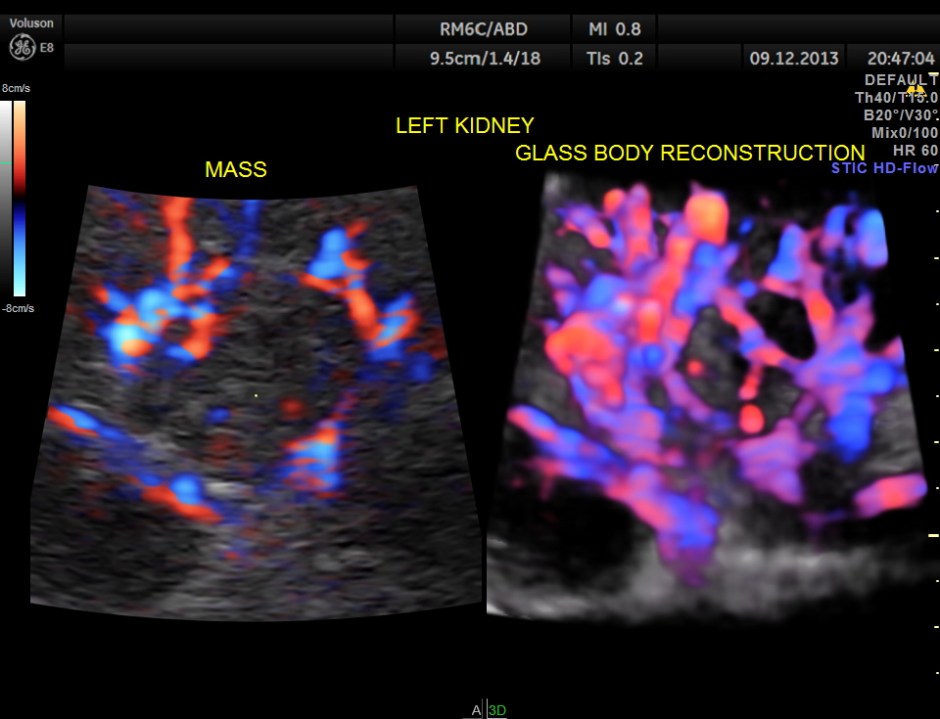

GLASS BODY RECONSTRUCTION IS GIVEN BELOW.

INCREASED VASCULARITY OF THE MASS IS WELL MADE OUT IN THIS GLASS BODY RECONSTRUCTION.